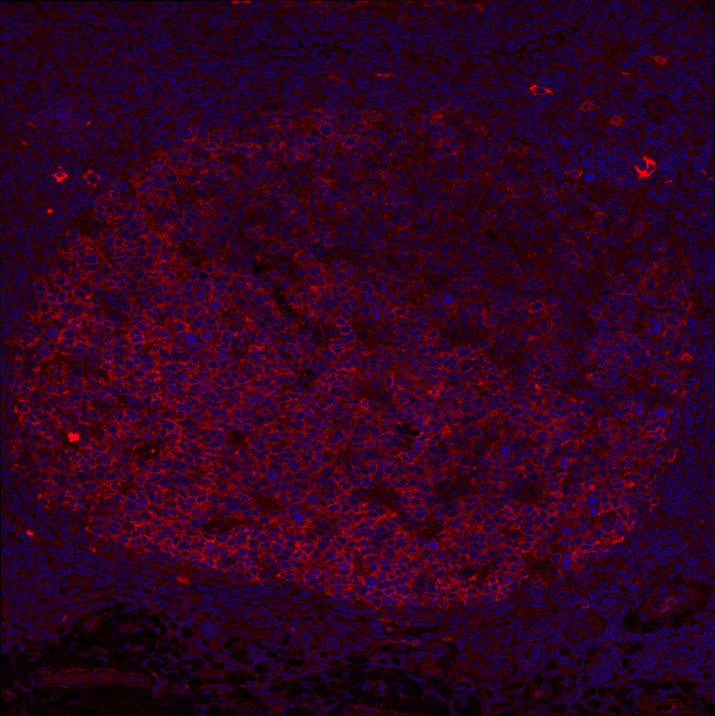

AICDA (AID) antibody IF Characterisation: Endogenous expression

Single immunofluorescence staining of the clone 5G9 mAB (red) in human paraffin embedded tonsil showing AID expression in germinal centres.